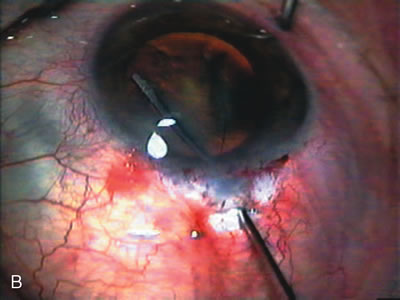

Cataract extraction by any technique performed in a patient with a pre-existing filter will have an effect on the previous filtering bleb.121–124 Bleb failure is more likely with ECCE compared with small-incision phacoemulsification.125 However, even patients undergoing topical anesthesia with clear corneal phacoemulsification and foldable IOL may experience bleb failure. One of three patients with a functioning filter and preoperative mean IOP of 12 mm Hg without antiglaucoma medications experiences bleb failure after lens extraction (Table 2). These patients require long-term drug therapy or bleb needling to control IOP. 126 Additional incisional glaucoma surgery may eventually be required in up to 10% of patients.127 Intraoperative iris manipulation may cause significant breakdown of the blood–aqueous barrier, resulting in inflammation that causes bleb failure. Even after uncomplicated clear corneal phacoemulsification, IOP may increase an average of 2 to 3 mm Hg due to bleb fibrosis.128 Approximately 20% of filtered patients require a long-term increase in glaucoma medications following uncomplicated clear corneal phacoemulsification with a foldable copolymer acrylic IOL129 (Fig. 3). In situations in which the bleb is not working at all, the eye will have a postoperative pressure spike that mimics that in the patient not having had a prior filtering procedure. In situations in which the bleb is marginal, the pressure spikes tend to be lower, and the final postoperative IOP tends to be around 50% higher than it was preoperatively. These patients require combined procedures in order to reestablish long-term filtration. In situations in which the bleb is very thin, polycystic, and associated with an IOP around 5 to 8 mm Hg on no antiglaucoma therapy; uncomplicated cataract extraction will have a minimal effect on the level of IOP. Patients with functioning glaucoma drainage implants usually have minimal long-term changes in IOP after uncomplicated cataract extraction.130

Fig. 3. Partial bleb failure following clear corneal phacoemulsification with foldable IOL. A. Preoperative bleb appearance prior to temporal lens extraction. Preoperative IOP was 12 mm Hg on no antiglaucoma medications. Time from 5-FU trabeculectomy surgery to lens extraction was one year. B. Bleb appearance 2 months after clear corneal cataract surgery with topical anesthesia. Following lens extraction, increased vascularity was noted along with decreased size of the filtering bleb. IOP increased to 20 mm Hg as early as 2 weeks after surgery, necessitating topical antiglaucoma therapy. C. High magnification view of bleb before lens extraction demonstrates diffuse pale bleb. D. High magnification view of bleb 2 months after surgery. There are vessels surrounding the nasal side of the bleb and the overall bleb size is smaller.